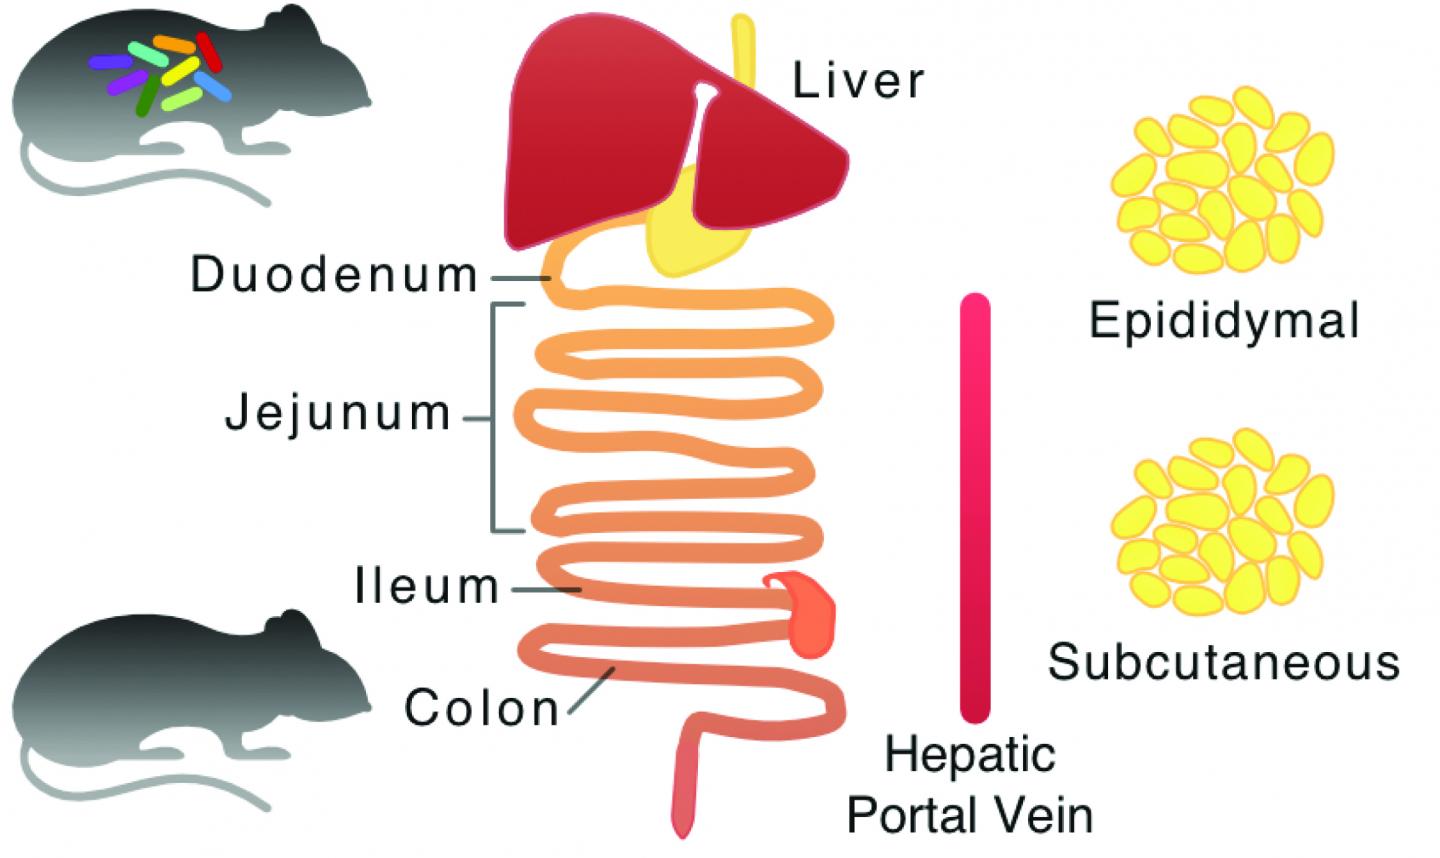

In un recente articolo pubblicato in Molecular Systems Biology, i ricercatori della Chalmers University of Technology, del Royal Institute of Technology e dell’Università di Göteborg in Svezia, hanno rivelato che la flora intestinale regola il metabolismo del glutatione.Lo studio, evidenziato sulla copertina della rivista, mostra un approccio integrativo realizzato attraverso dati raccolti da una combinazione di proteomica, trascrittomica e metabolomica, per rivelare le differenze metaboliche tra topi privi di batteri e topi normali.

Per lo studio è stata creta una mappa generica del metabolismo dei topi e sono stati generati al computer, modelli di tessuto-specifici dei topi. Attraverso l’integrazione di dati sperimentali, i ricercatori hanno scoperto che la flora batterica nel piccolo intestino consuma glicina, che è uno dei tre aminoacidi necessari per la sintesi del glutatione.

Per confermare i risultati delle simulazioni computerizzata, è stato misurato il livello degli amminoacidi nella vena porta dei topi. Inoltre, un livello inferiore di glicina è stato osservato nei tessuti del fegato e del colon, che indica che la flora intestinale regola il metabolismo del glutatione, non solo nel piccolo intestino, ma anche nel fegato e nel colon.